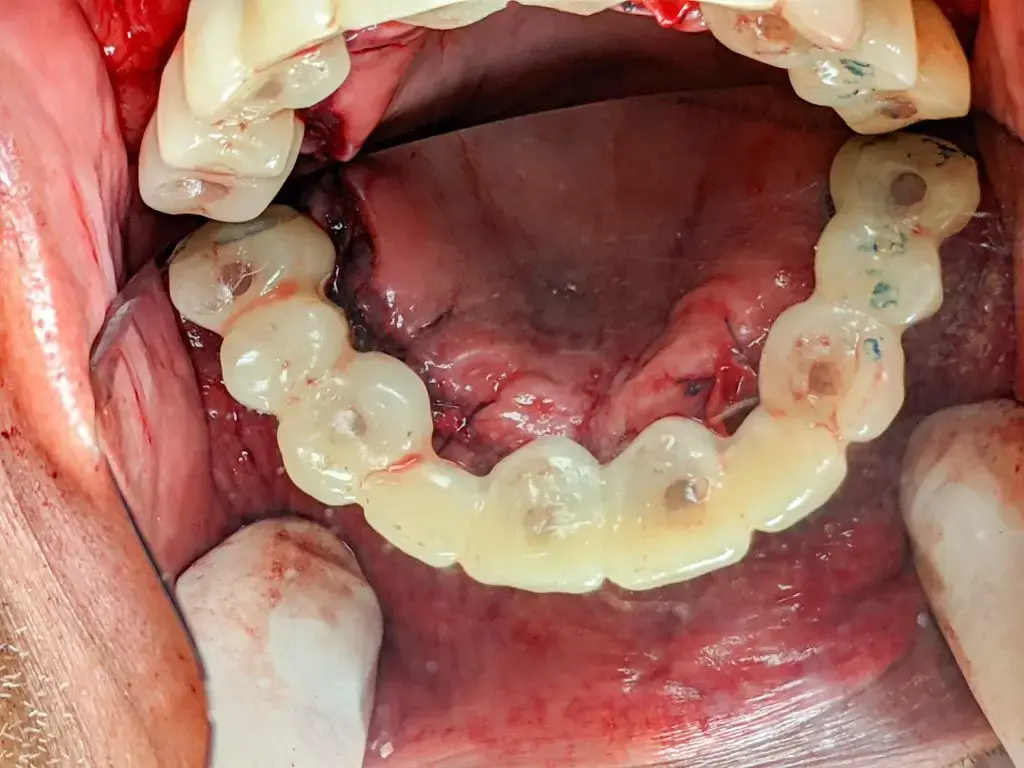

There is a philosophy of minimal bone reduction surging in full-arch dentistry. Most full-arch, immediate-load, cases completed today do not follow this philosophy. They involve leveling the bone to a flat surface and meeting that surface with a prosthetic, often with what is considered excessive alveoloplasty. There is an alternative and it is a part of the GuidedSMILE family of products – GuidedSMILE Natural.

GuidedSMILE Natural follows the same beginning as standard CHROME GuidedSMILE cases – Pin Guide, Fixation Base, and Osteotomy Guide. Then, a special scalloped guide aids with the visualization and contouring of the alveoli’s reduction to create socketing for the tissue and prosthetic. This is technique sensitive and we like to send one of our experienced technicians chairside for guidance for at least your first case.

The prosthetic is delivered during surgery and then converted in several months using a duplicate RAPID Appliance that was picked up during surgery.

A Patient Case Study

CHROME Natural Maxillary